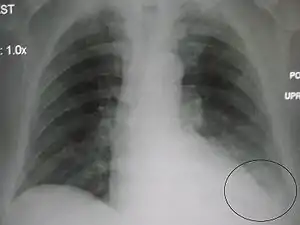

| A parapneumonic effusion (circled), due to a left lower lobe pneumonia. |

The criteria for a complicated parapneumonic effusion include Gram stain–positive or culture-positive pleural fluid, pleural fluid pH <7.20, and pleural fluid LDH that is greater than three times the upper limit of normal of serum LDH.[2] Diagnostic techniques available include plain film chest x-ray, computed tomography (CT), and ultrasound. Ultrasound can be useful in differentiating between empyema and other transudative and exudative effusions due in part to relative echogenicity of different organs such as the liver (often isoechogenic with empyema).